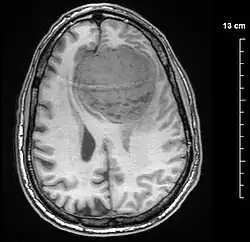

![]() | |

An MRI of the brain, demonstrating the appearance of a meningioma | |

Meningiomas are visualized readily with contrast CT, MRI with gadolinium,[23] and arteriography, all attributed to the fact that meningiomas are extra-axial and vascularized. CSF protein levels are usually found to be elevated when lumbar puncture is used to obtain spinal fluid. On T1-weighted contrast-enhanced MRI, they may show a typical dural tail sign absent in some rare forms of meningiomas.[18]